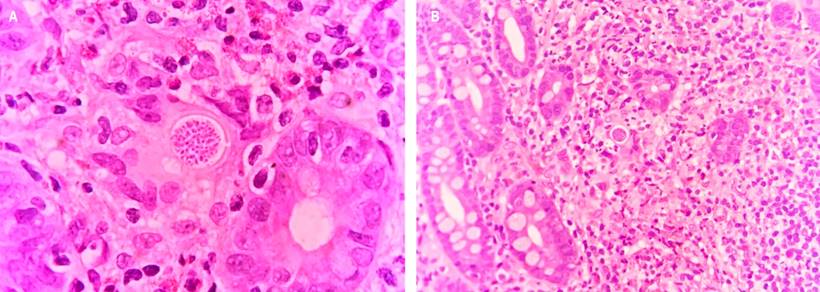

The anatomopathological study of the endoscopic biopsy of the lesion identified acute and chronic ulcerated duodenitis with a granulomatous component and abundant blastoconidia compatible with Coccidioides spp (Figure 2).